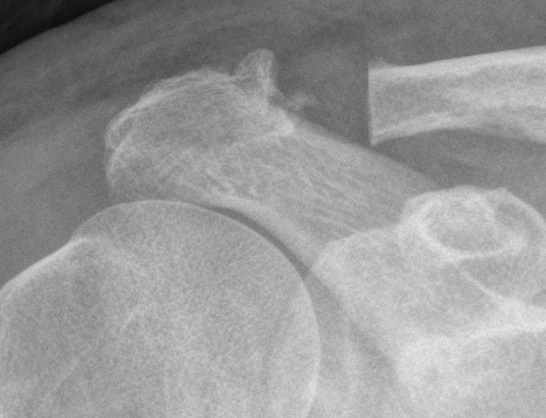

Xray

Zanca view - AP 10° cephalic tilt with 50% penetration

Acromioclavicular osteoarthritis

Stein et al. J Should Elbow Surg 2001

Grade I: Normal

Grade II: Capsular distension, bone marrow edema, mild joint narrowing

Grade III: Capsular distension, joint space narrowing, marginal osteophytes

Grade IV: Markedly abnormal ACJ with large osteophytes